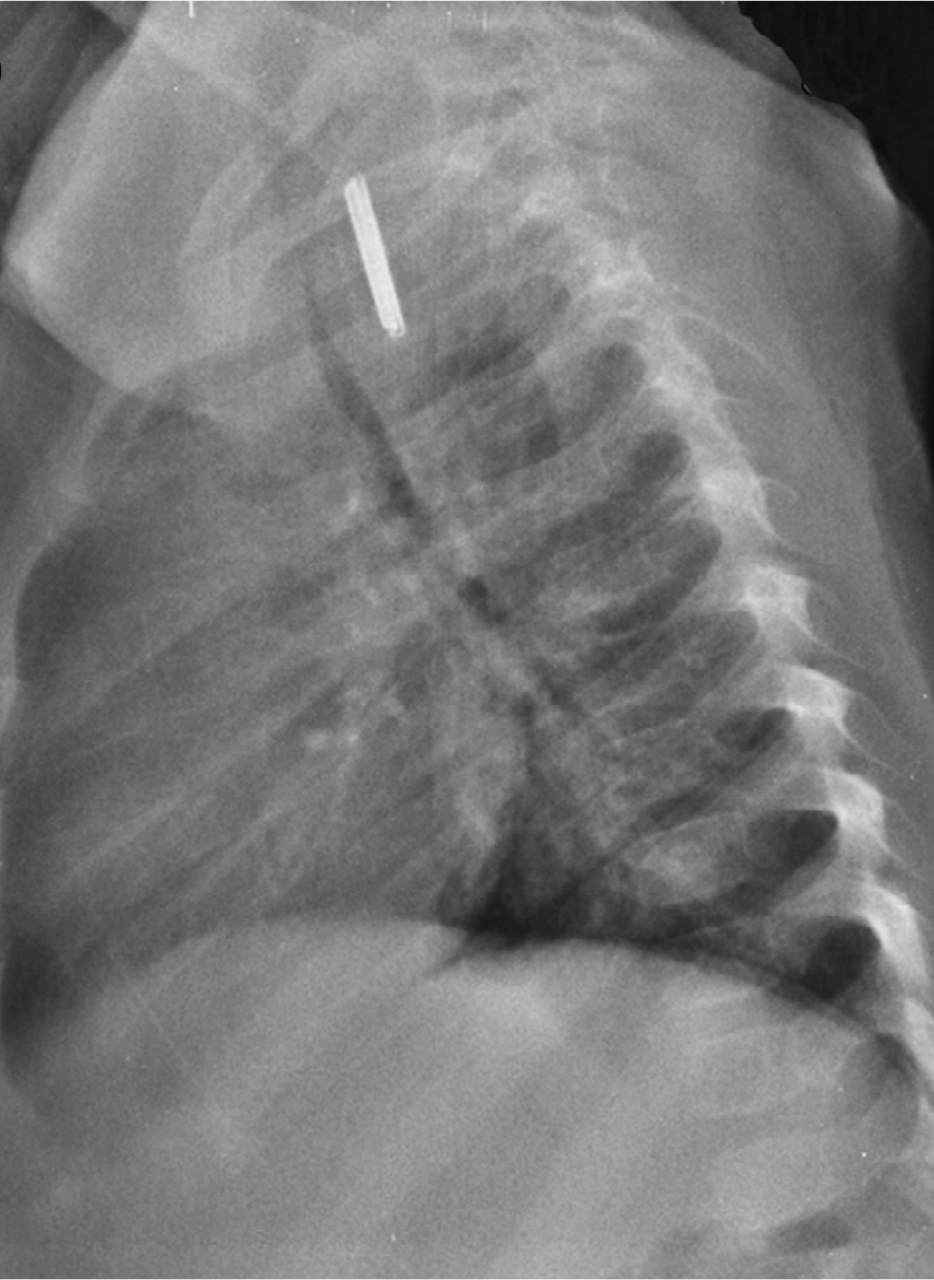

Question 4 : Voici la radiographie du thorax de l’enfant. Interprétez-la.

Surtout sur la radiographie de profil, nous pouvons bien voir que la trachée est en avant du corps étranger

Sur la radiographie de profil, on voit que le corps étranger est sur le trajet de l’œsophage0

Sur la radio de face, les deux poumons ont la même taille. Rappel : le trapping se voit sur une radiographie en expiration où l’air n’arrive pas à sortir du côté bloqué

Signe très important : les piles boutons ont un double contour (sur les radios de face) et une petite marche d’escalier sur le contour (sur les radios de profil)

Il n’y a pas de double contour sur une pièce de monnaie

Il s’agit ici d’un corps étranger œsophagien. Un corps étranger œsophagien peut avoir causé un syndrome de pénétration initialement par deux mécanismes possibles : soit le corps étranger a entraîné une cyanose en bloquant le larynx lors de son passage dans l’hypopharynx avant la déglutition, soit il y a eu une véritable inhalation, puis expulsion lors d’un effort de toux et déglutition. C’est ce qu’il se passe dans la majorité des cas de syndrome de pénétration avéré avec fibroscopie bronchique blanche : le corps étranger a été expulsé, puis recraché ou dégluti.

La grande crainte lors d’un corps étranger œsophagien est la pile bouton, qui peut faire des dégâts irréparables en quelques minutes sur la muqueuse œsophagienne par contact. Elle peut être différenciée à la radio d’une pièce de monnaie (corps étranger beaucoup plus fréquent), grâce au double contour que l’on aperçoit facilement sur les radios de face et de profil. Une pièce de monnaie présente un contour lisse. Insérer image « Figure3.jpg ».